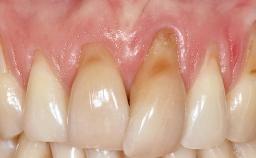

It is sometimes necessary to remove and replace compromised implants. This case is a clear example of the need for multiple steps to achieve an optimal therapeutic result for patients with non-salvageable implants. It illustrates how the lost soft and hard tissues were rebuilt in a sequence that improved the healing of the hard tissues and assured their long-term stability. The 35-year-old healthy patient presented with clinical attachment loss on the proximal and lingual surfaces of the natural dentition. Some gingival recession was present on natural teeth, particularly in the posterior sextants (S1, S3, S4, and S6).

Prosthesis Type FDP